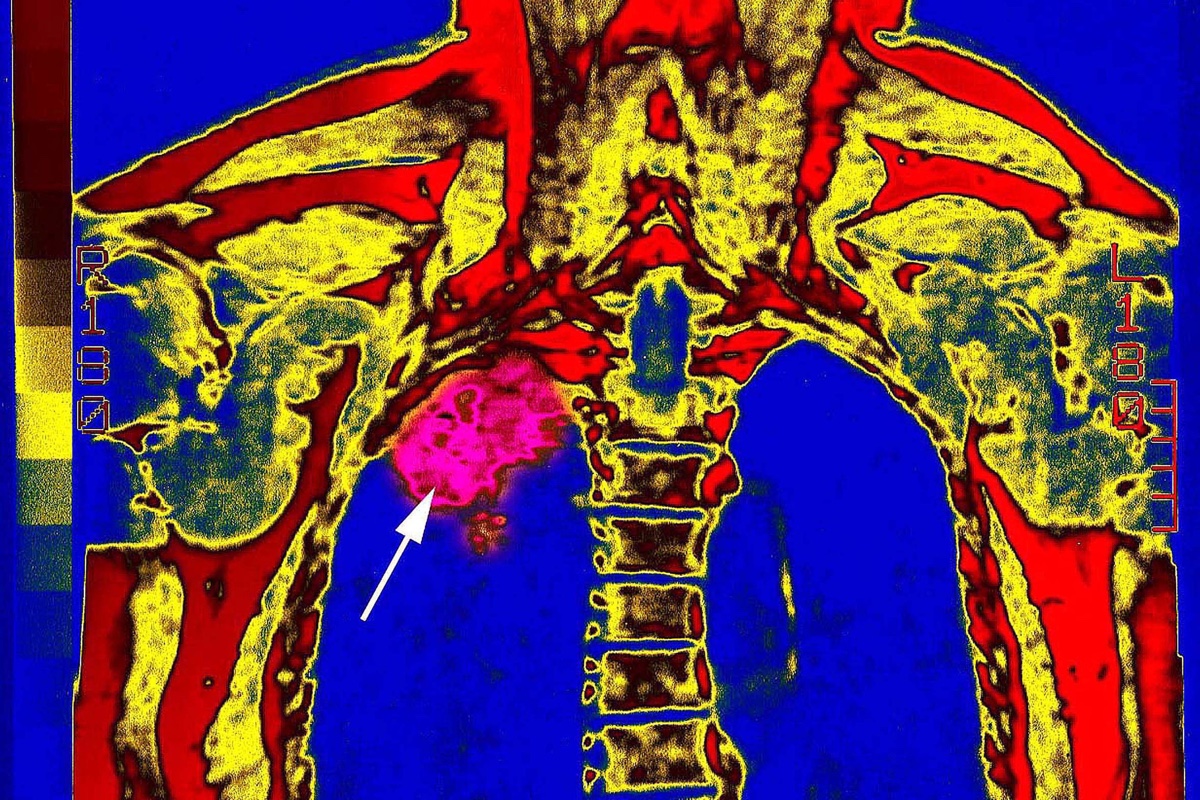

Lung Cancer

Lung Cancer: Signs, Symptoms, Types & Treatment

Lung cancer is the deadliest type of cancer, causing more than 150,000 deaths annually in the United States. Smoking is the No. 1 cause of lung cancer.